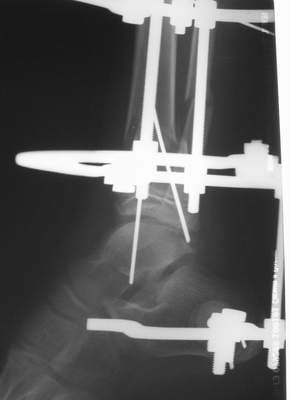

Нашел в комп-ре схожий случай:

1) з/репозиция, 2) фиксация 2 спицами, 3) аппарат, 4) фиксационные

спицы удалены...

А можно было наложить аппарат и по поводу ложного сустава...

По крайней мере не было бы укорочения (пусть и в 2 см)...